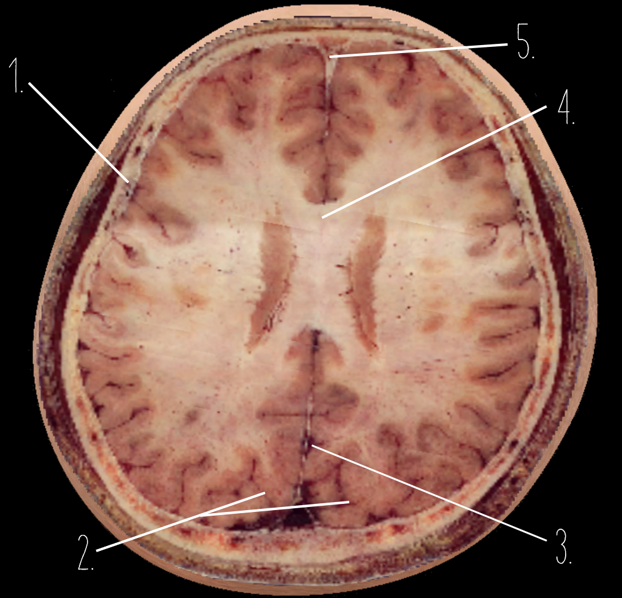

1

Frontal Bone

2

Frontal Lobe

3?

Falx Cerebri

4?

Gray Matter

5?

White Matter

6?

Sulcus

7?

Gyrus

8?

Fissure